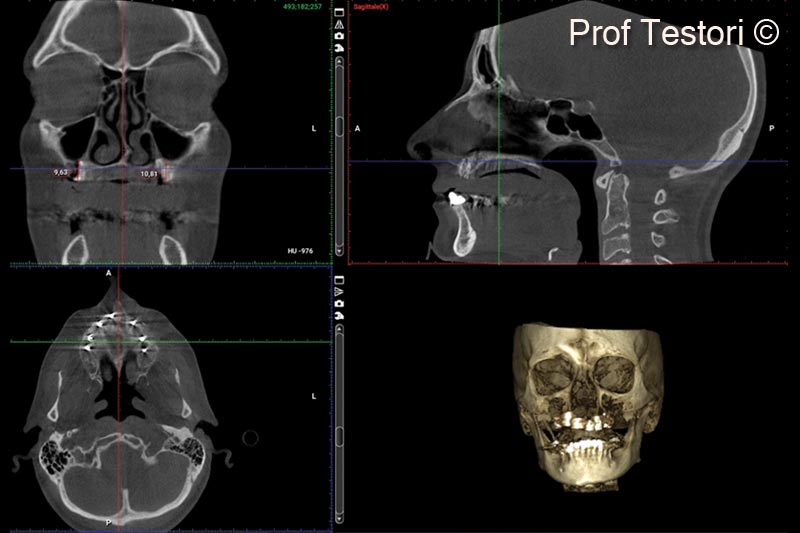

12. 6-months follow-up CBCT performed before implant placement

13. 6-months follow-up CBCT performed before implant placement